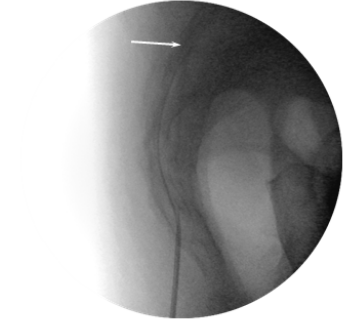

On the assumption of localization of the affected roots, we used classic caudal access to locate the introducer. From paramedian access, a puncture was performed in the hiatus sacralis; the Tuohy 16G introducer was placed at a level not higher than S3. The RCE electrode was moved through the introducer in the direction of the lumbar roots through the dorsal epidural space (Figure 1). There was no special protocol of fluid administration for hydrodissection or facilitating electrode conduction. The working tip of the electrode (15 mm) was located in the projection of the lateral canal opposite the exit zone and just dorsal to the affected nerve root, at the exact location of the determined nerve impairment or slightly proximal (Figure 2). After placement of the electrode, sensory stimulation was performed at 50 Hz, in the range of 0.3-0.5 V, and a typical sensation response was obtained that accurately overlapped the painful area of the patient. Because theventral and dorsal branches are very close in the impact zone, motor stimulation with 2 Hz was often also effective, but with a slightly higher voltage, most often within 1 V. Provided that the impedance in the impact zone corresponded to a normal value (200–400 Ohm), the PRF was started in monopolar mode with the following characteristics: frequency 2 Hz (20 ms pulse, 480 ms pause), amplitude 65V, exposure time 360 ​​sec, temperature in the action zone not exceeded 42 degrees Celsius. After the procedure, a water-soluble steroid was administered (dexamethasone, 8 mg) through the catheter (Figure 3). Patients remained in the hospital for at least 2 hours, upon expiration of the control period, and in the absence of warning signs, they were discharged home.

Figure 3 Lateral view. Contrast material spread into the dorsal and ventral epidural space. Arrow – tip of the RCE electrode.